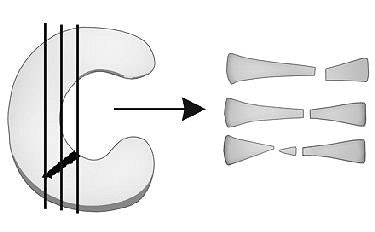

![]() |

| A schematic diagram showing the marching cleft sign for detecting radial meniscal tears. Harper KW, Helms CA, Lambert HS, Higgins LD, "Radial Meniscal Tears: Significance, Incidence, and MR Appearance" (AJR 2005; 185:1429-1434). |